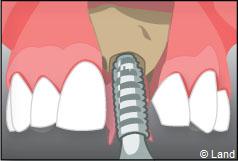

Exemple d’un implant unitaire pour remplacer une dent antérieure manquante.

Le chirurgien-dentiste après une anesthésie locale pratique une incision, puis il décolle la gencive pour accéder à l’os alvéolaire.

Ensuite il prépare l’emplacement de l’implant dans l’os en passant plusieurs forets de diamètre croissant. Le forage de l’os se fait à vitesse maîtrisée et lente sous irrigation, pour respecter la structure osseuse et éviter tout échauffement de celle-ci. Le praticien arrête lorsqu’il a obtenu un puits d’un diamètre très légèrement inférieur à l’implant à poser.

L’implant est placé dans l’os le plus souvent par vissage et doit avoir une liaison forte avec l’os. Le praticien replace alors la gencive et pose des points de suture.

Il faut attendre après la pose de l’implant, l’ostéo-intégration, qui peut durer plusieurs mois. L’implant va se souder complètement avec l’os et contrairement à la dent naturelle, il n’y a pas de souplesse ou de mobilité physiologique dues au ligament alvéolo-dentaire.

À l’issue de sa mise en place chirurgicale, une bague de cicatrisation en titane peut être directement vissée sur l’implant. Ainsi une seconde chirurgie ne sera pas nécessaire pour découvrir l’implant.